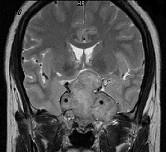

问题 女,26岁,垂体腺瘤切除术后,左眼视物模糊,请根据所提供图像,选择最可能的诊断()

选项 A.鞍区脑膜瘤 B.(垂体)复发性嫌色细胞腺瘤 C.脊索瘤 D.神经纤维瘤 E.颅咽管瘤

答案 B